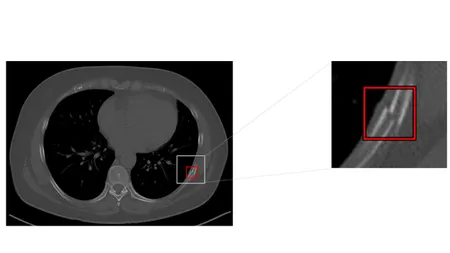

胸部CT画像から肋骨骨折の候補を検出して表示する機能です。医師が再確認することで見落しを低減します。